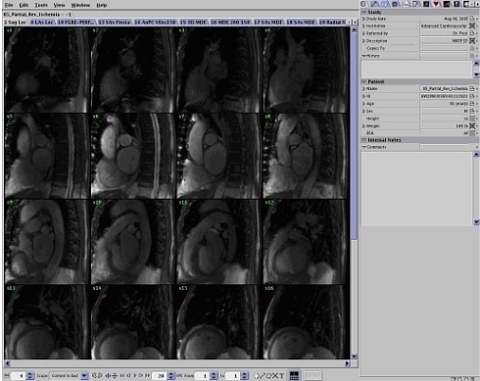

The ReportCARD 4 application is a reviewing and reporting application for Magnetic Resonance Imaging (MRI) data, in particular, Cardiac MRI. It provides simultaneous reviewing and report creation of cardiac MR exams with multiple series containing DICOM images. Multi-phase cardiac images are automatically displayed as time-lapse animations with no user interaction.